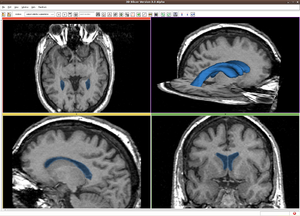

| + | |[[Image:RssVentricle.png|thumb|300px|RSS result for Brain MR image]] | ||